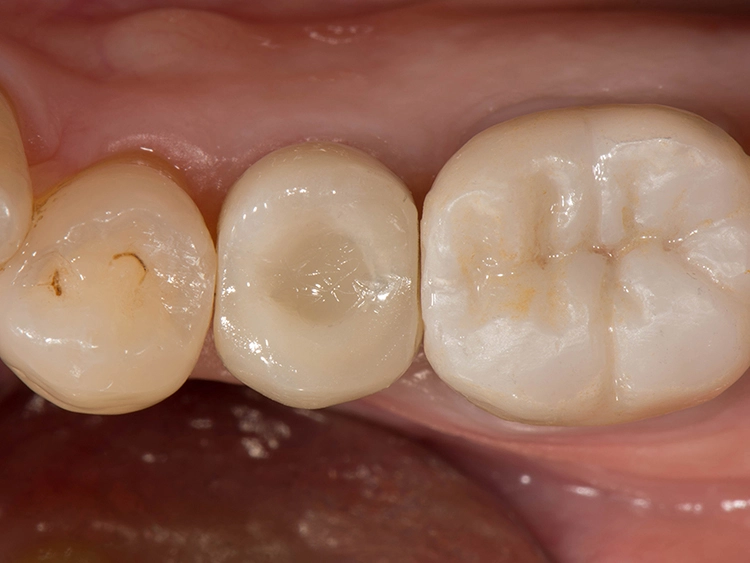

Zweiteilige Implantatsysteme würden darüber hinaus mit einer höheren prothetischen Flexibilität punkten, weil die Aufbauten individueller gestaltet werden können. Dr. Röhling: „Das kann ein Vorteil sein, wenn etwa die prothetische Achse korrigiert werden muss.“ Hinzu kommt, dass bei Anwendung von zweiteiligen Systemen eine Zementierung, die für Fehlerquelle anfällig gesehen wird, entfällt, da sie eine reversibel verschraubte Befestigung erlauben, während bei einteiligen Implantaten die Suprakonstruktion nur zementiert gestaltet werden kann (siehe Fallbeispiel, Abbildungen 1 bis 10).